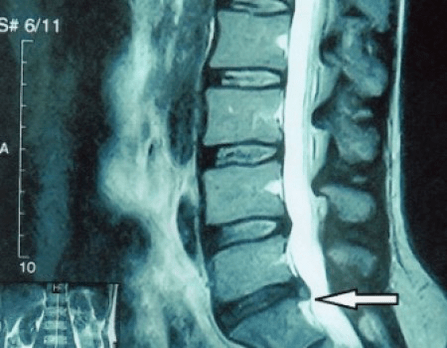

In typical cases, osteochondrosis of the cervical and cervicothoracic spine occurs as described above.Therefore, the main stage of diagnosis has been and remains the identification of the patient's complaints, establishing the presence of concomitant muscle spasms by simple palpation of the muscles along the spine.Is it possible to confirm the diagnosis of osteochondrosis by radiological examination?

An "X-ray" of the cervical spine, and even with functional tests of flexion and extension, does not show cartilage, since its tissue transmitsFragile and dehydrated intervertebral discs.Functional tests can confirm the diagnosis of cervical spine instability.

Since the discs themselves can only be seen using CT or MRI, magnetic resonance and X-ray CT are indicated to clarify the internal structure of cartilage and formations such as protrusions and hernias.Thus, with the help of these methods, a diagnosis is made accurately and the tomography result is an indication, or even a topical guide, for surgical treatment of a hernia in the neurosurgery department.

- if you have a hernia, you need to dynamically monitor it, conduct regular MRI scans, avoid increasing its size or carry out modern minimally invasive surgical treatment, because without exception, all conservative methods of treating exacerbation of osteochondrosis leave the hernia in place and eliminate only temporary symptoms: inflammation, pain, shooting and muscle spasms.